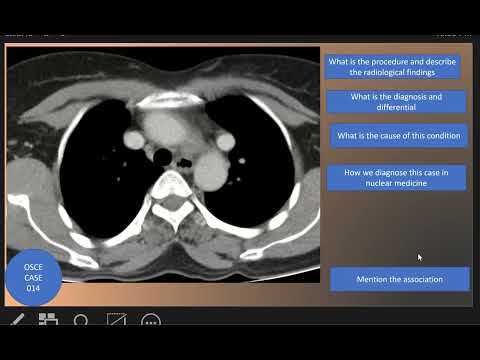

OSCE Case 014 : Superior vena caval duplication